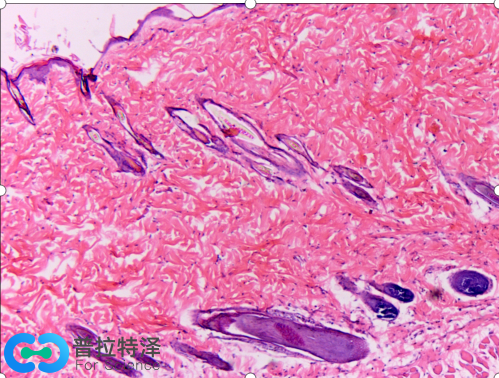

傳統(tǒng)的馬松染色使用四種染料,使組織切片呈現(xiàn)三種顏色,準(zhǔn)確的稱呼是馬松三色染色法(Masson's trichrome stain)。第一種染料是蘇木精,配制成Weigert氏鐵蘇木精液,與HE染色相似,這里的蘇木精也是染細(xì)胞核,由于用的是鐵蘇木精,細(xì)胞核染色后不是經(jīng)典HE染色的藍(lán)色,而是呈現(xiàn)暗灰黑色,這是第一色。第二種染料酸性品紅和第三種染料麗春紅配制成混合溶液,這兩種紅色染料染與HE染色中的伊紅相似,可以染細(xì)胞質(zhì)為紅色,這是第二色。第四種染料是甲基藍(lán)(苯胺藍(lán)也可),染膠原纖維為藍(lán)色,這是第三色。經(jīng)典的馬松染色效果與HE染色對(duì)比如下圖:

這是小鼠皮膚組織兩種病理染色圖片,左邊是馬松三色染色,右邊是HE染色。

右邊HE染色呈現(xiàn)藍(lán)色和紅色兩種顏色,而左邊馬松三色染色有灰黑色、紅色和藍(lán)色三種顏色,尤為明顯的是藍(lán)色。左圖中的大片藍(lán)色區(qū)域是皮膚上皮組織,結(jié)構(gòu)較為疏松,含有較多的膠原纖維,被馬松三色染色法中的甲基藍(lán)染成藍(lán)色。這樣染色后,可以清晰地看到毛孔在上皮結(jié)蹄組織中的分布。因此,被染成藍(lán)色的細(xì)胞外基質(zhì)(通常都含有膠原纖維)就能和細(xì)胞以及其他組織形成鮮明的對(duì)比,從而易于觀察。在某些病理狀態(tài),如心肌梗死,肝硬化和腎纖維化等情況下,病變的細(xì)胞會(huì)被結(jié)締組織取代,用馬松染色能很好地發(fā)現(xiàn)病變部位,并能對(duì)病變進(jìn)行定量的評(píng)估。因此,直到今天,馬松染色依然是組織學(xué)和病理學(xué)中活躍的染色方法,并出現(xiàn)了幾種改良的馬松染色,使得染色效果更加理想。